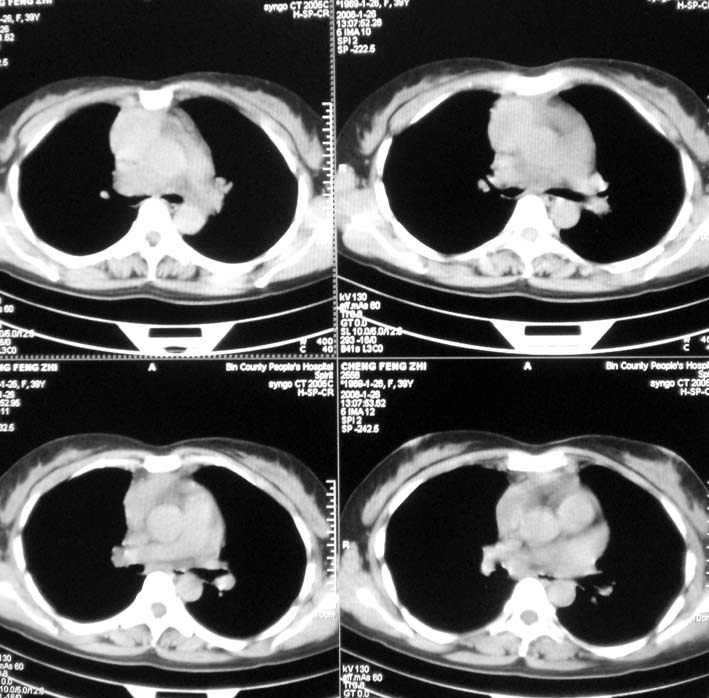

以下是引用guoke在2008-1-27 14:15:00的发言:[br]纵隔增宽,纵隔内血管境界不清,心包积液,考虑纵隔淋巴瘤.[br]

以下是引用随光逐影在2008-1-27 15:52:00的发言:[br]1)考虑为:淋巴瘤。建议:行进一步检查。2)心包积液。